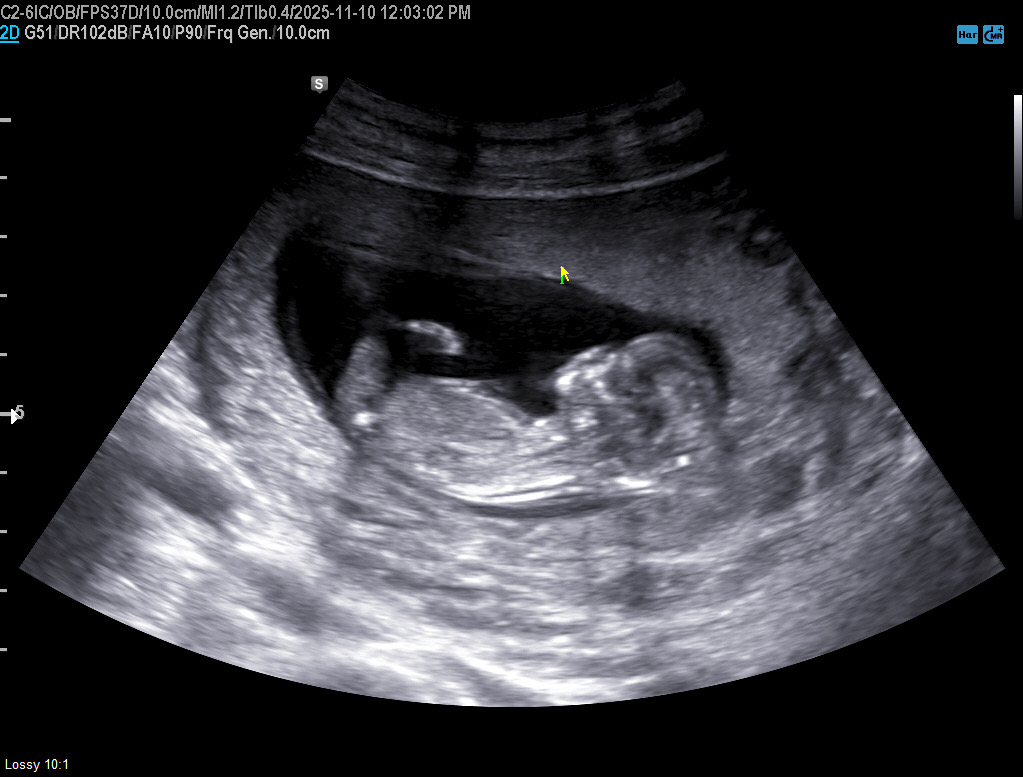

12주2일 초음파 각도법 봐주셔요!

궁금하고만요!🤓